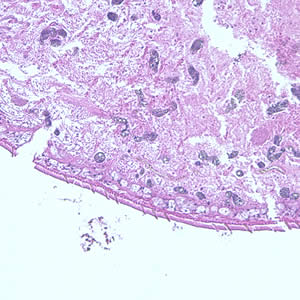

A patient complaining of intermittent symptoms including coughing up blood, fever, and other vague “flu-like” symptoms saw a physician. The patient reported working at a sushi restaurant and eating a raw crab on a dare (Figure A shows a crab similar to the one that the patient ate). Blood tests were ordered and results included peripheral eosinophilia of 10% and a history of bilateral pneumothorax (free air or gas in the pleural cavity). A biopsy yielded a cyst containing a structure 5 mm in length and 2 mm in width. Figure B (40×) and Figure C (100×) show a hematoxylin and eosin (H & E) stained section of the specimen. Figure D (400×) shows an object which measured 80-90 µm by 40-45 µm. Similar objects were found in low numbers in sections of lung tissue. What is your diagnosis? Based on what criteria?

Figure C